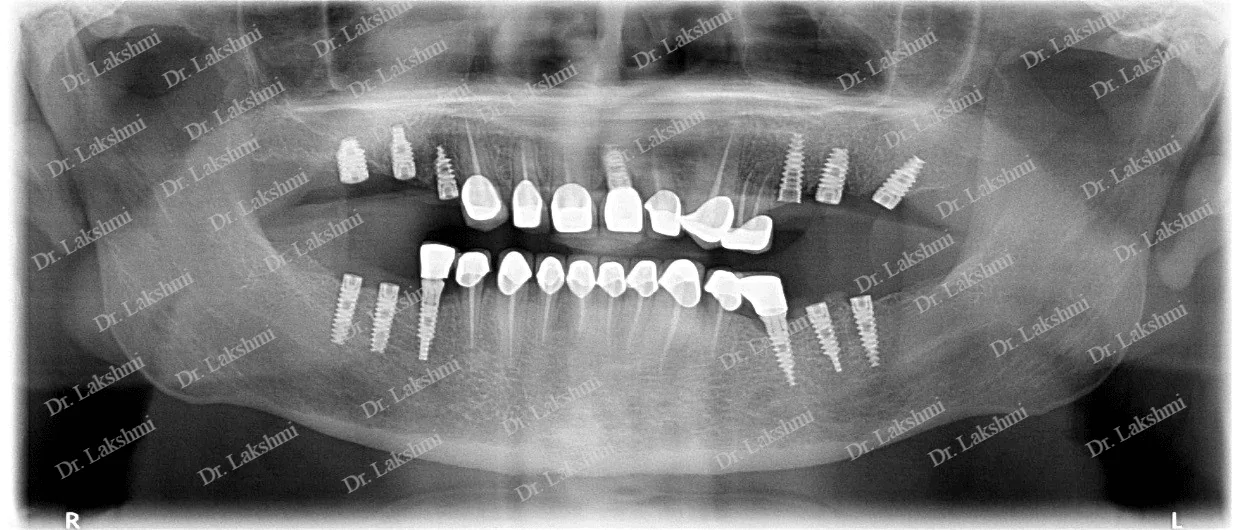

X-Ray Image

Dental implants have come to define modern dentistry in the last few decades. Dental implants are cemented to the jawbone and an abutment is used as a support for the dental crown that is placed over it. There are a single piece, two-piece and three-piece abutments available for implants. Titanium fuses naturally with the jawbone and that makes it a perfect fit as an implant. There are several dental implant techniques available to opt from, for a patient. The freedom to opt also depends on the condition of the jawbone and the gum.

is the brainchild of Dr.P.S.Lakshmi, conceived and established after her return from the U.S. in the year 2002. As the name suggests the team perfect smile under the tutelage of Dr.P.S.Lakshmi has imbibed the latest changes that have taken place in the treatment with dental prosthetics and dental implants. Perfect Smile has the state-of-the-art infrastructure with in-house latest X-ray diagnostic facilities and can carry out the most severely compromised and advanced bone loss cases with ease. With vast experience of over 2 decades, they can do any type of complex post-implant prosthetics.